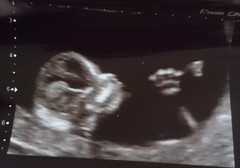

All went well today! Moved forward a few days so now 12+6 and due December 13th.

Little monkey was upside down to begin with, I had to wiggle around, they kept on pushing their legs off the side and successfully flipping back over, arms and legs were everywhere so the scan took a little while to get measurements 😂

Great scan pics @TootsyBella84 😄

Tootsy that's beautiful Grin

Hello baby @TootsyBella84 xxx